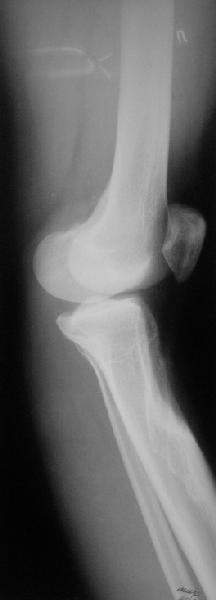

Продолжение обсуждения, начатого в октябре прошлого года (см. здесь) Наконец-то оперировали эту пациентку. Биопсию сделали - опухолевого ничего нет. Пока все участвовавшие в обследовании смежные специалисты и ортопеды сошлись, что это молокальная монооссальная фиброзная дисплазия. 20 марта наложили аппарат, сделали чрескожную остеотомию. К 3 апреля все докрутили. Сегодня заштифтовали. Начальные и итоговые снимки в приложении. Рекурвацию можно было еще немного больше устранить, и чуть кзади сместить диафиз. Но вроде и так ничего выглядит, по сравнению с тем, что было. Комментарии приветствуются.

ничего не понимаю в детской и ортопедии, но в боковой проекции нет рекурвации,

а даже немного гиперкоррекция, что по-моему есть хорошо. Кортикалы по задней стенке совпадают, диафиз на одну неправду кзади.

Есть клиновидный диастаз, контакт основных отломков на очень небольшой площади только в задненаружном отделе. Так что там скорее межотломковая дистракция, а не компрессия.